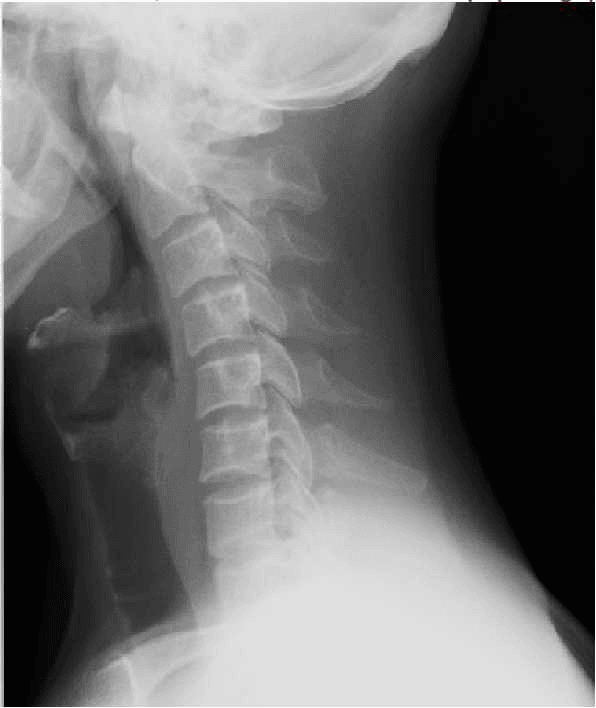

ENTORSE CERVICALE (Inversion de la courbure physiologique)

IMAGE NORMALE